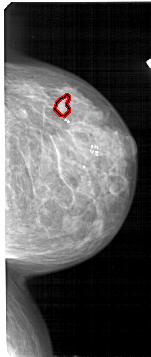

FILE: A_1713_1.RIGHT_CC.OVERLAY

TOTAL_ABNORMALITIES 1

ABNORMALITY 1

LESION_TYPE CALCIFICATION TYPE PLEOMORPHIC DISTRIBUTION CLUSTERED

ASSESSMENT 4

SUBTLETY 1

PATHOLOGY BENIGN

TOTAL_OUTLINES 1

BOUNDARY